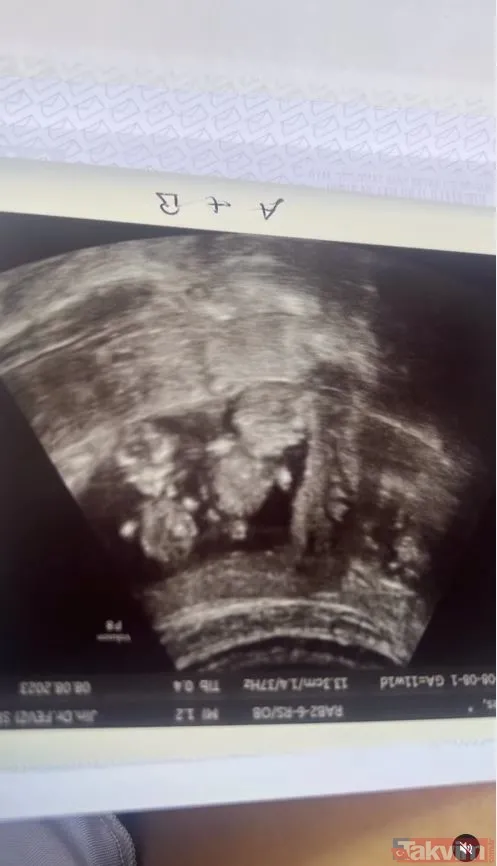

İbrahim Tatlıses de iddiaları doğrularken ikiz bebek müjdesini vermişti. İbrahim Tatlıses açıklamasında şu ifadeleri kullanmıştı

"Yasemin ikiz bebek bekliyor, bebeklerden biri kendisini saklamış ve iki gün önce kendisini gösterdi. Yasemin, 2,5 aylık hamile, cinsiyetleri henüz belli değil. Derya Tuna haberi öğrendiğinde gözyaşlarına boğuldu, çok mutluyuz"